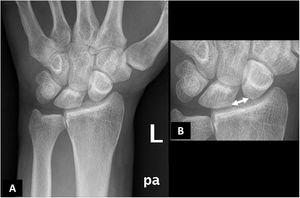

The case presented is that of a 30-year-old left-handed male who consulted for episodes of intermittent chronic pain in the dorsal aspect of the left wrist, which partially subsided after taking anti-inflammatory drugs. The condition began following an accidental fall from his height 2 years earlier, for which he did not consult. A posteroanterior wrist X-ray showed a scapholunate diastasis of 3.5 mm and a rotatory subluxation of the scaphoid (Fig. 1). The study was completed with ultrasound and magnetic resonance imaging (Figs. 2 and 3), which demonstrated a complete rupture of the dorsal component of the scapholunate ligament. The patient was referred to the Hand Unit for consultation, where surgical treatment with arthroscopic ligamentoplasty was decided.

Posteroanterior plain radiograph of the left wrist (A) with magnified detail (B). There is a significant diastasis between the lunate and scaphoid bones of the carpus (double-headed arrow), which in the manual measurement was 3.5 mm. In addition, a rotatory subluxation of the scaphoid bone (B) is seen, which is an indirect indicator of scapholunate ligament injury, although it is visible in other injuries of different wrist stabilisers.